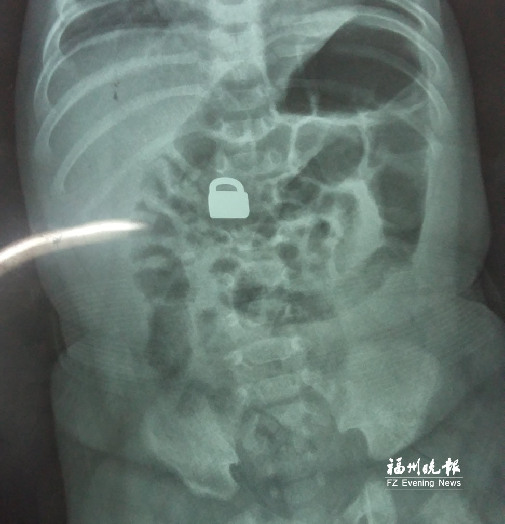

7.25龍巖當?shù)蒯t(yī)院拍的X光片顯示,平安鎖在寶寶體內(nèi)。

這名60天大的“神奇寶寶”來自龍巖,哥哥也只有兩歲。7月25日,兄弟倆的媽媽突然發(fā)現(xiàn)寶寶胸前掛著的平安鎖不見了,便問小哥哥是否看到弟弟的平安鎖。小哥哥回答,他把平安鎖塞到弟弟嘴里了。媽媽趕緊檢查寶寶嘴巴,沒有發(fā)現(xiàn)平安鎖。雖然寶寶沒有任何癥狀,但媽媽還是帶著他去當?shù)蒯t(yī)院檢查。拍片結(jié)果顯示,平安鎖真的在寶寶體內(nèi)。

“X光片顯示,那是一把1.5厘米×0.9厘米的平安鎖,有指甲蓋大小,已經(jīng)到了寶寶的小腸處?!?月28日,陳惠萍見到寶寶時,吃了一驚,“他真的好小,被抱在媽媽懷里,眼睛微微睜開,我估計他的世界還是混沌的,沒想到就已經(jīng)接受了這么大的挑戰(zhàn)。”